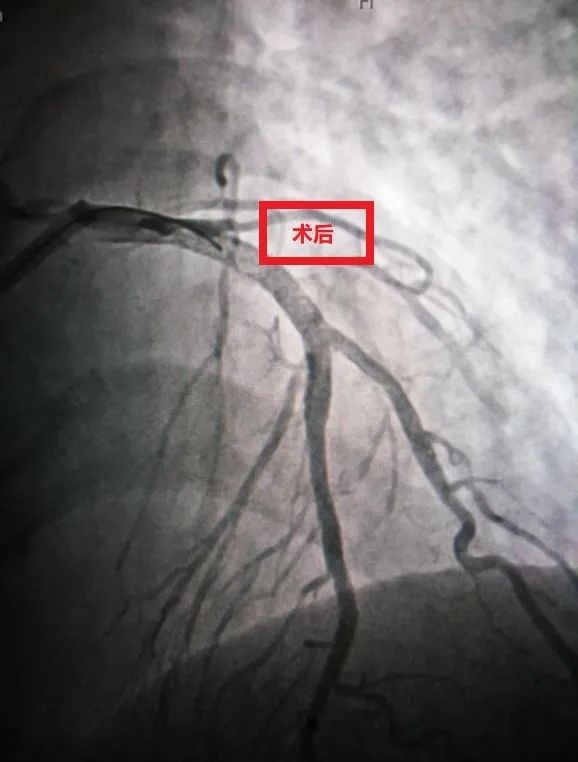

第一次术后

第二次术前

第二次术后